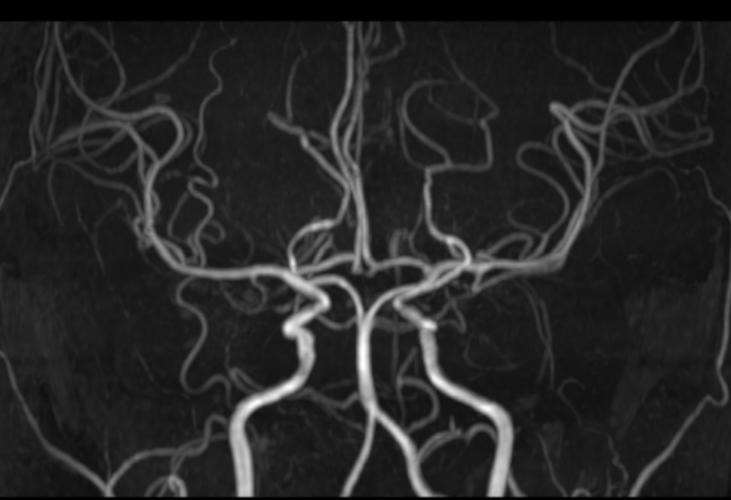

MRA(磁共振血管成像):血管的“透明管道工”

- 作用:MRA是MRI的一种特殊应用,无需造影剂(或少量造影剂)即可清晰地显示血管的结构、走行、有无狭窄、闭塞、动脉瘤或畸形等,它主要看“血管通不通,有没有明显病变”。

- 在脑梗中的应用:MRA可以帮助寻找脑梗的病因,比如大脑中动脉重度狭窄、颈内动脉闭塞等大血管病变导致的脑梗。

- 解释:MRA虽然能清晰显示颅内主要的大血管(如颈内动脉、大脑中动脉、大脑前动脉、大脑后动脉及其主要分支),但对于更细小的穿通动脉(直径约0.2-1mm)的显示能力有限,这些穿通动脉深穿脑组织,主要负责供应基底节、丘脑、脑干等关键区域的血液。